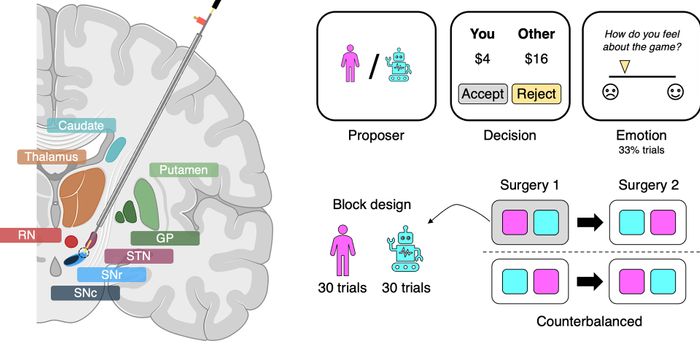

AUG 26, 2024NeuroscienceA groundbreaking study published in the New England Journal of Medicine has demonstrated the remarkable potential of bra ...

JUN 17, 2024Neurosciencerobotic deep brain stimulation, deep brain stimulation, paralysis, pediatrics